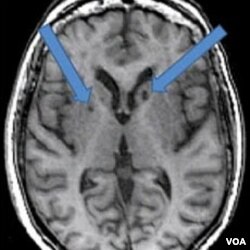

Hasil MRI atas otak pasien yang pernah terkena stroke dua kali. Panah menunjukkan adanya bintik-bintik gelap yang dulunya adalah sel-sel sehat yang mati akibat gumpalan darah yang masuk ke otak.

Pada hasil pemindaian pasien stroke, tampak lubang gelap berisi cairan. Psikolog syaraf Adam Brickman pada Fakultas Kedokteran Universitas Columbia, mengatakan ada bintik-bintik gelap yang dulunya adalah sel-sel sehat yang mati akibat gumpalan darah yang masuk ke otak.